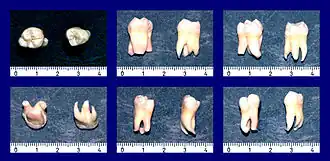

Weisheitszähne weichen häufiger als andere Zähne von ihrer charakteristischen anatomischen Form ab. So treten Weisheitszähne mit drei oder fünf Höckern auf. Auch die Anzahl der Wurzeln ist unterschiedlich. Sie können miteinander verwachsen oder hakenförmig gebogen sein, so dass eine gegebenenfalls notwendige Extraktion der Zähne erschwert ist. In seltenen Fällen wachsen hinter den Weisheitszähnen noch überzählige Weisheitszähne, so genannte Distomolaren, auch Neuner genannt.[2]